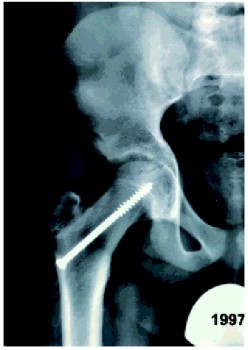

Marja van Wijk, een 12-jarig meisje met blanco voorgeschiedenis komt in augustus 2001 op het spreekuur orthopedie. Sinds oktober 2000 heeft ze last van haar linker heup na een val tijdens handbal. Ze blijft pijn in de heup en lies houden en heeft moeite met lopen. De huisarts schrijft Mensendieck-therapie voor. Drie maanden later wordt er een anteroposterior (AP) röntgenfoto van het bekken gemaakt. Deze wordt als niet-afwijkend beschreven, waarop de huisarts fysiotherapie voorschrijft. De klachten verbeteren tot ze in juni 2001 valt, waarna de klachten hevig verergeren. Het been is dan onbelastbaar; paracetamol helpt. Elf maanden na het ontstaan van de klachten komt ze op het spreekuur orthopedie. De klachten zijn afgenomen, maar ze loopt mank, heeft moeite om na het opstaan op gang te komen en kan maximaal een halfuur lopen. Ze heeft nog geen menarche gehad. Uit lichamelijk onderzoek blijkt dat ze een antalgisch looppatroon heeft met het linker been in exorotatie. De linker heup heeft een passieve flexie van 90° met een positieve Drehman (exorotatie bij flexie) en een opgeheven endorotatie. De functie van de rechter heup is niet afwijkend. Bij röntgenonderzoek van het bekken is zowel op de AP-opname als op de Lauenstein-opname (heup in 90° flexie en maximale abductie) links een ECF zichtbaar ( figuur 1). Deze blijkt achteraf ook op de foto van januari 2001 te zien. Vergeleken met de opname van toen is de afglijding toegenomen.

Beide patiënten werden acuut opgenomen en kregen een loopverbod. Ze werden de volgende dag geopereerd. De operatie bestond uit epifysiodese (fixatie in situ van de femurkop met een gecannuleerde schroef). Marja werd links en Anouk beiderzijds geopereerd. Bij controle na zes weken bleken de twee meisjes geen pijnklachten meer te hebben. Dat het te laat stellen van de diagnose ernstige gevolgen kan hebben, illustreert de volgende casus.

Het doel van de behandeling is het laten verdwijnen van de epifyse (epifysiodese), zodat de kop niet verder afglijdt. Hiermee wordt een stabiele groeischijf bereikt, waardoor verdere afglijding en de daarbij mogelijke complicaties voorkomen worden.6 Er zijn meerdere behandelmethodes. Epifysiodese in situ wordt meestal uitgevoerd met één gecannuleerde schroef. Dit geeft voldoende stabiliteit ( figuur 2).124567 Eventueel kan eerst geprobeerd worden de afglijding te verminderen. Daarnaast bestaat de mogelijkheid van epifysiodese met correctie-osteotomie, waardoor de verhouding tussen epifysiolyse en femurschacht verbeterd wordt. In het uiterste geval zal een artrodese uitgevoerd worden.